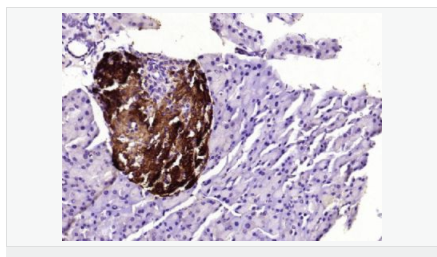

image.png